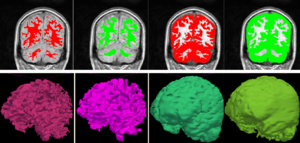

Atlas Guided Identification of Brain Structures by Combining 3D Segmentation and SVM Classification

Publication: MICCAI 2006, LNCS 4191, pp. 209–216, 2006. PDF

Authors: Ayelet Akselrod-Ballin, Meirav Galun, Moshe John Gomori, Ronen Basri, and Achi Brandt

Institution: Department of Computer Science and Applied Math, Weizmann Institute of Science, Rehovot, Israel and Dept. of Radiology, Hadassah University Hospital, Jerusalem, Israel

Background/Purpose: This study presents a novel automatic approach for the identification of anatomical brain structures in magnetic resonance images (MRI). The method combines a fast multiscale multi-channel three dimensional (3D) segmentation algorithm providing a rich feature vocab ulary together with a support vector machine (SVM) based classifier. The segmentation produces a full hierarchy of segments, expressed by an irregular pyramid with only linear time complexity. The pyramid provides a rich, adaptive representation of the image, enabling detection of various anatomical structures at different scales. A key aspect of the approach is the thorough set of multiscale measures employed throughout the segmentation process which are also provided at its end for clinical analysis. These features include in particular the prior probability knowl- edge of anatomic structures due to the use of an MRI probabilistic atlas. An SVM classifier is trained based on this set of features to identify the brain structures. We validated the approach using a gold standard real brain MRI data set. Comparison of the results with existing algorithms displays the promise of our approach.